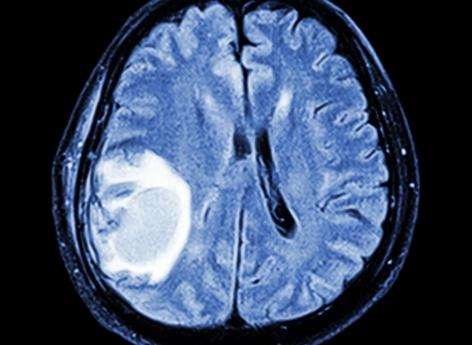

Mais en août 2018, une étude menée par l’Assurance maladie révèle que ce médicament est suspecté de multiplier jusqu'à 20 (après 5 années de traitement), et même plus, la probabilité de méningiomes, c’est-à-dire de tumeurs intracrâniennes, chez les femmes traitées longtemps et à hautes doses. Généralement bénignes, ces tumeurs peuvent occasionner de graves séquelles comme des troubles de la mémoire, de l’épilepsie ou une perte du goût et de l’odorat.

Une IRM cérébrale devra systématiquement être prescrite pour les patients débutant leur traitement, et envisagée pour la poursuite du traitement. Tant que le traitement est maintenu, l'IRM suivante interviendra au plus tard 5 ans après la première, puis tous les deux ans si l'IRM précédente est normale.